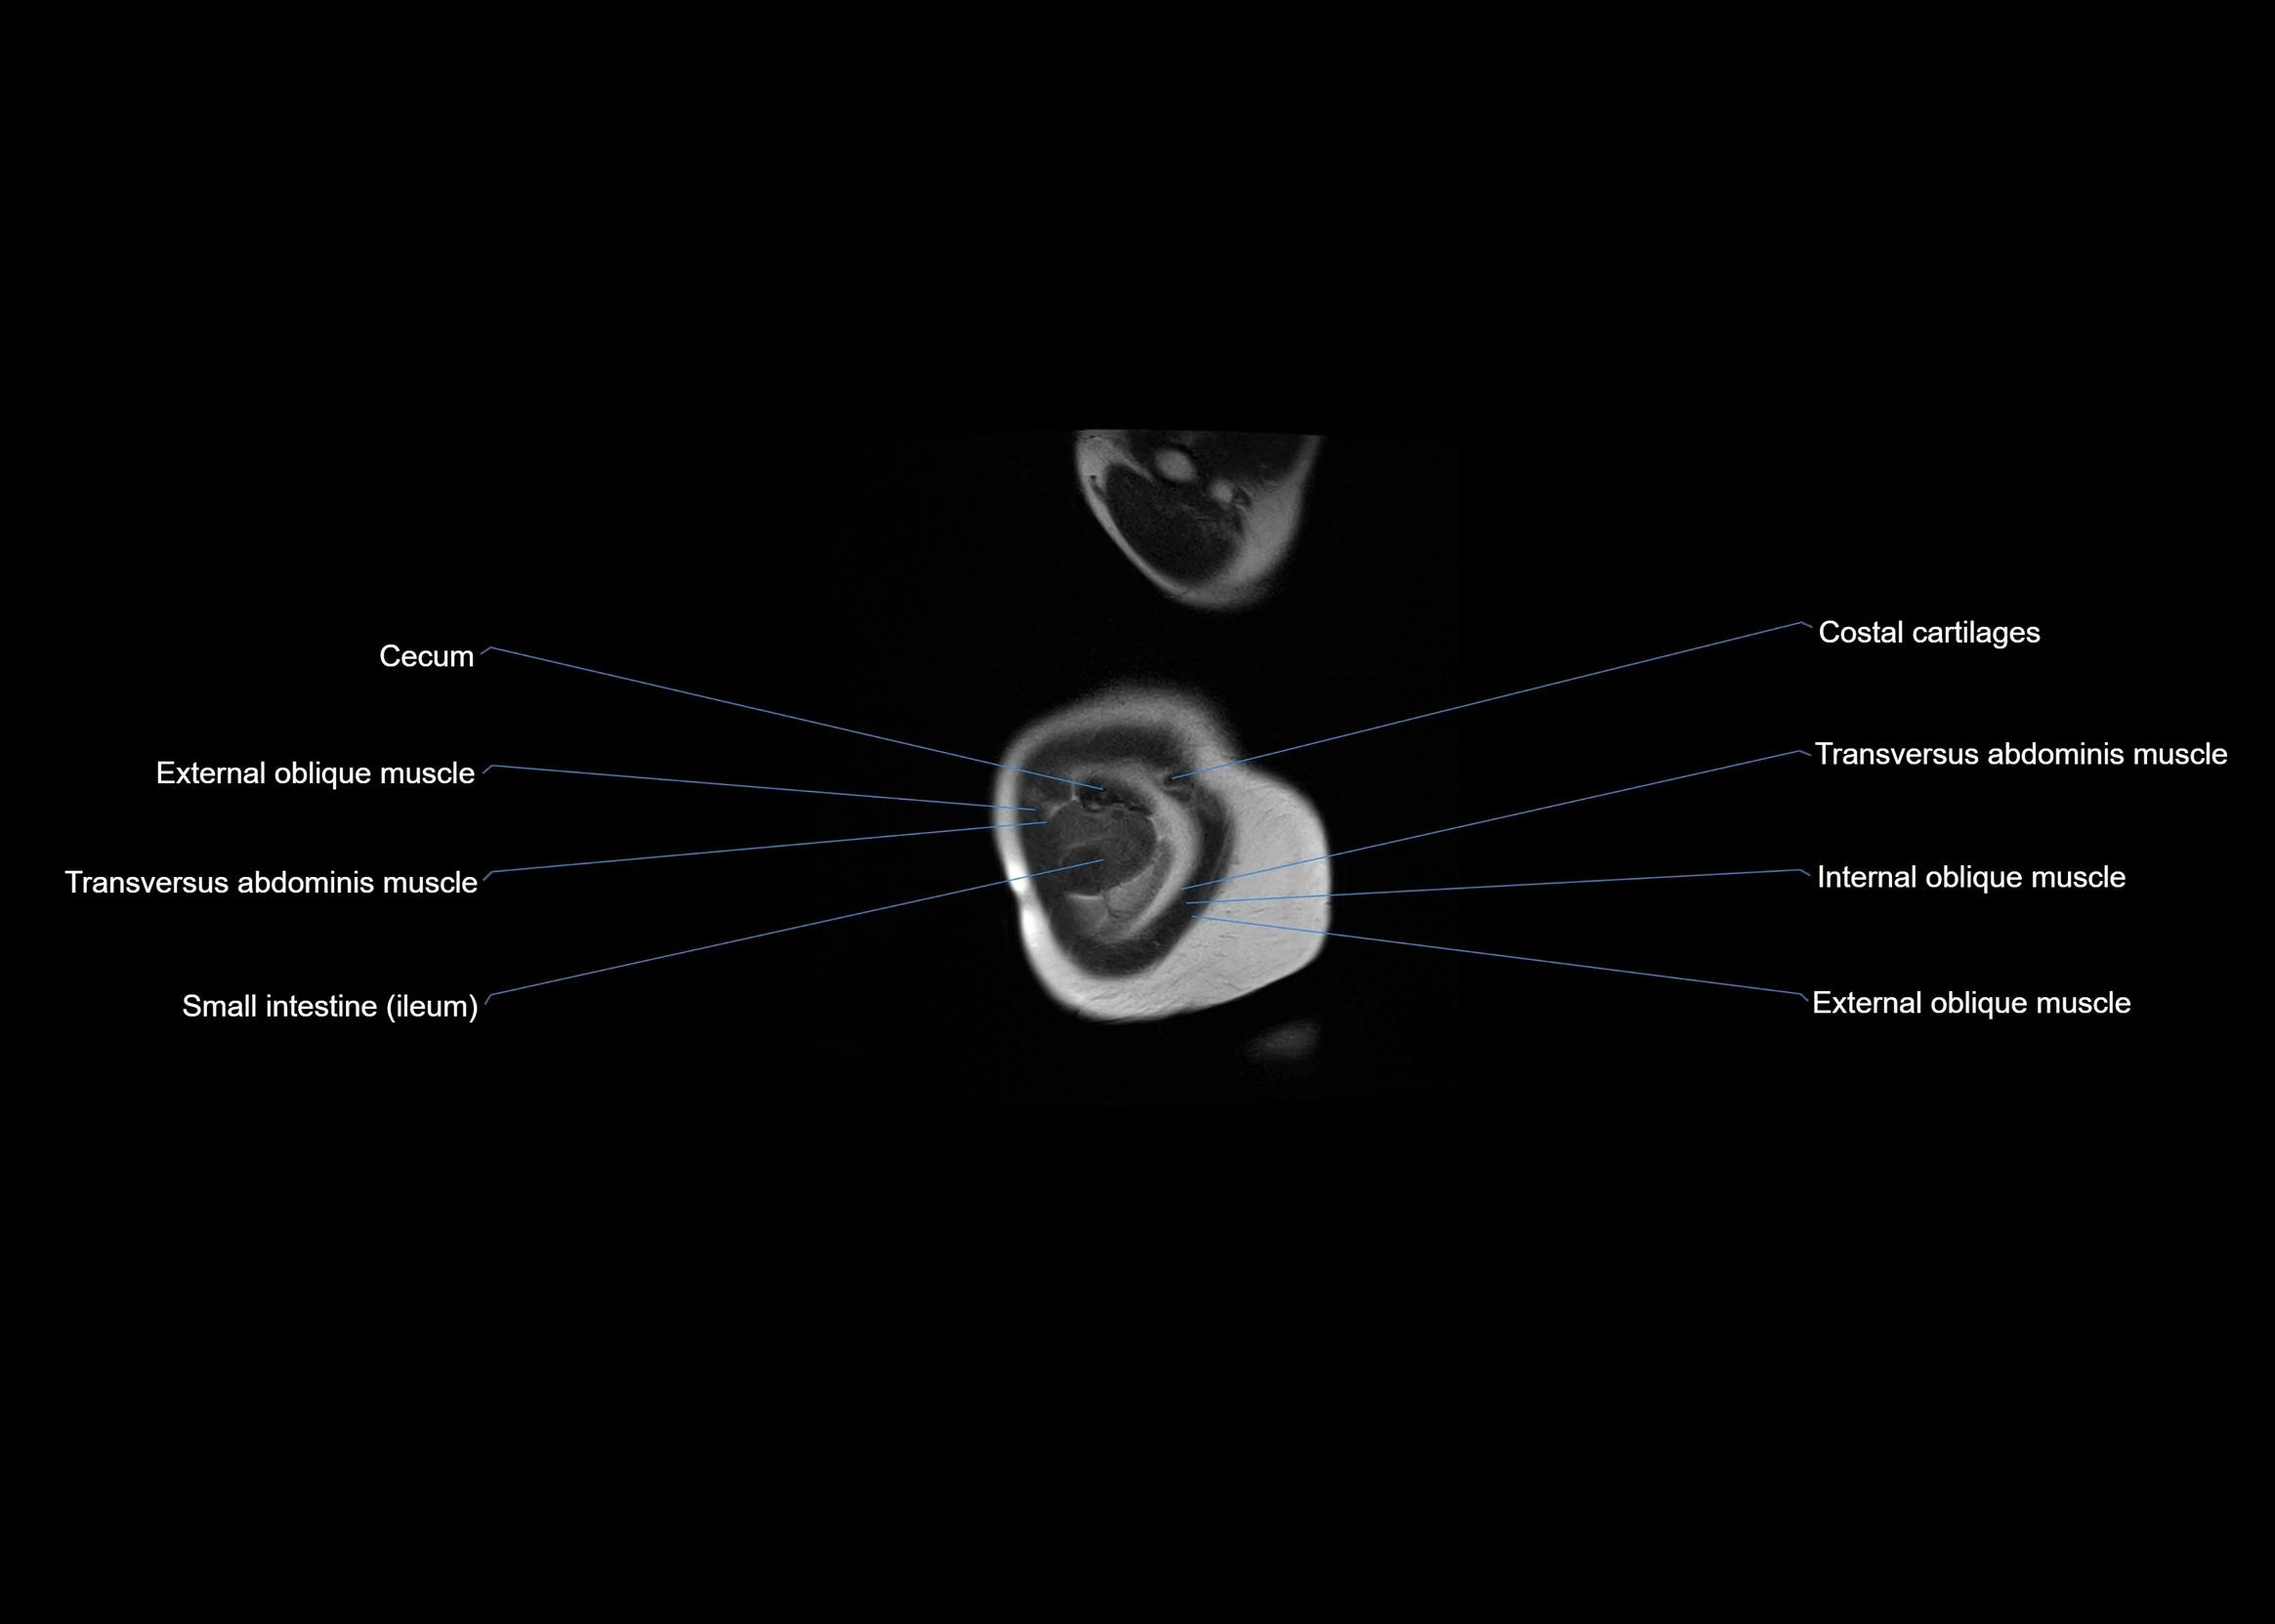

- Cecum

- External oblique muscle

- Internal oblique muscle

- Transversus abdominis muscle

- Ileum